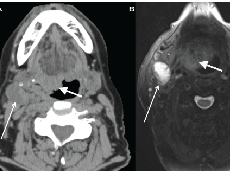

Prospective Study Links HPV Detection in the Mouth to Head and Neck Cancer

A new study confirms that infection with HPV 16 precedes the development of head and neck cancer.

Genome Study Yields Clues to Head and Neck Cancers

Researchers have surveyed the genetic changes in nearly 300 head and neck cancers, revealing some previously unknown alterations that may play a role in the disease, including in patients whose cancer is associated with the human papillomavirus (HPV).